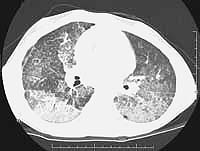

TABLE OF PROCEDURES AND COMPLICATIONS

Despite some improvement with the bronchial washings, she has continued to require oxygen (at 3L/min continuous) and has failure to thrive. Her weight is 22.6 kg (< 5%ile) and height (128 cm ~5%ile). Her echocardiogram is normal and she is not polycythemic as a result of hypoxemia. The pulmonary function tests show a moderate restrictive defect. Her most recent high resolution CT scan shows persistent ground glass infiltrates and crazy paving despite bronchial lavages.

CT

scans: original - after first wash compared to most recent HRCT.

LEFT

CT SCAN (June), RIGHT

CT SCAN (August)